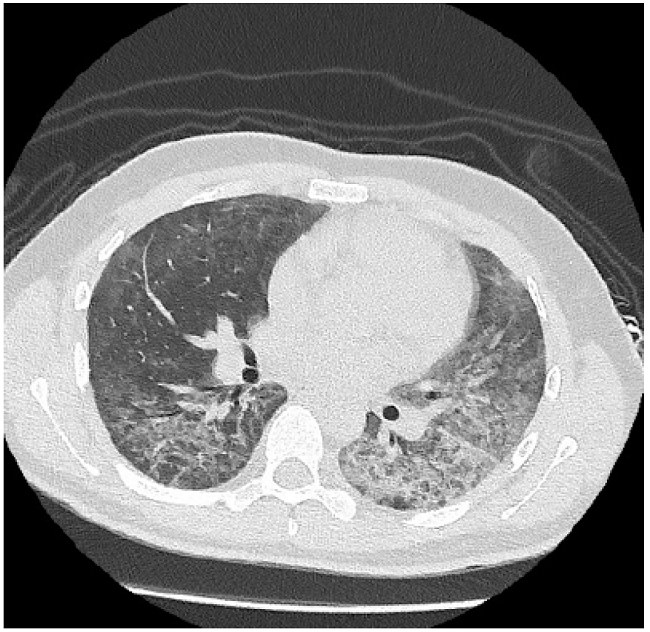

A las 48 horas de hospitalización se confirma diagnóstico de VIH, siendo derivado al hospital de referencia para continuar estudio y tratamiento. En dicho centro se realiza tomografía axial computarizada que confirma patrón de neumonía tipo Pneumocistis jirovecci, tal como se evidencia en las Figuras 2 y 3. Por normativa local, el inicio de la triterapia se indica en el hospital de referencia.